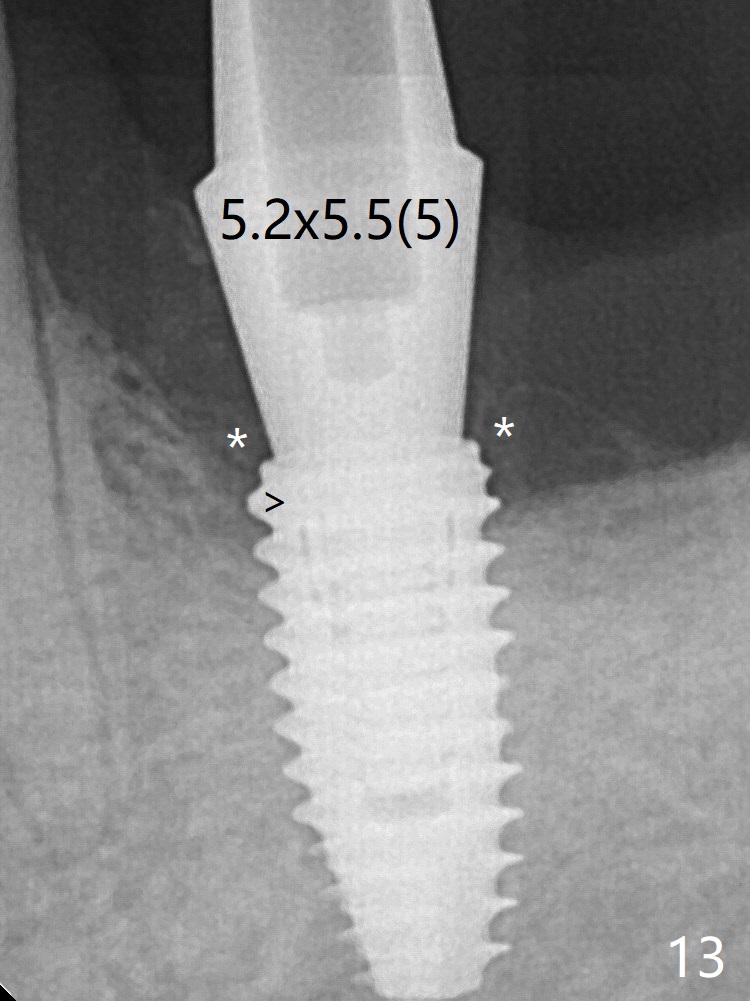

After insertion of a definitive abutment (6.5x5.5(4) mm), more allograft is placed coronally (Fig.3 *). There is no apparent thread exposure 4 months postop (Fig.10). A narrower abutment with longer cuff appears to be completely seated (without a gap, Fig.13 >), probably avoiding contact with the regenerated crestal bone (*).